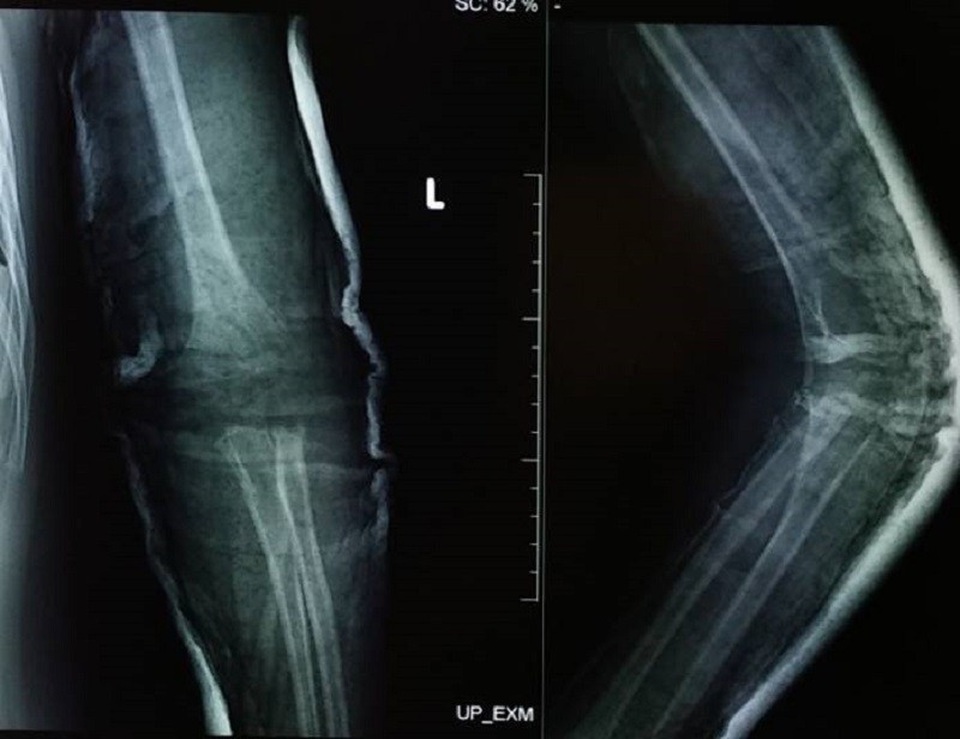

Ngày 15/4, thông tin từ bệnh viện cho hay, qua thăm khám, chẩn đoán hình ảnh xác định, bệnh nhi bị gãy chỏm quay khuỷu tay trái. Tuy nhiên, do không được điều trị kịp thời nên chỏm quay bị hoại tử và dính chặt bằng mô xơ, gây biến chứng giới hạn cử động khớp.

Các bác sĩ đã phải thực hiện cuộc phẫu thuật cắt bỏ chỏm quay, giải phóng khớp khuỷu tay bằng phương pháp cơ học. Sau phẫu thuật, cánh tay bệnh nhi đã cử động tốt, cháu đang được tập vật lý trị liệu để phục hồi vận động.